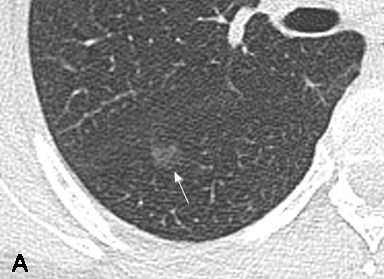

Small ground-glass lung nodules are common. Be careful, it might be a very invasive tumor. This article tells you more about the small signs that may draw your attention.

• Invasive lesions were found in 55.3% of lung adenocarcinomas with subcentimeter pGGNs

• Lesion size, vessel changes, and tumour-lung interface showed different among histopathologic subtypes

• Vessel changes, unsmooth margin and clear tumour-lung interface were predictors for lesion invasiveness

Article: CT and histopathologic characteristics of lung adenocarcinoma with pure ground-glass nodules 10 mm or less in diameter